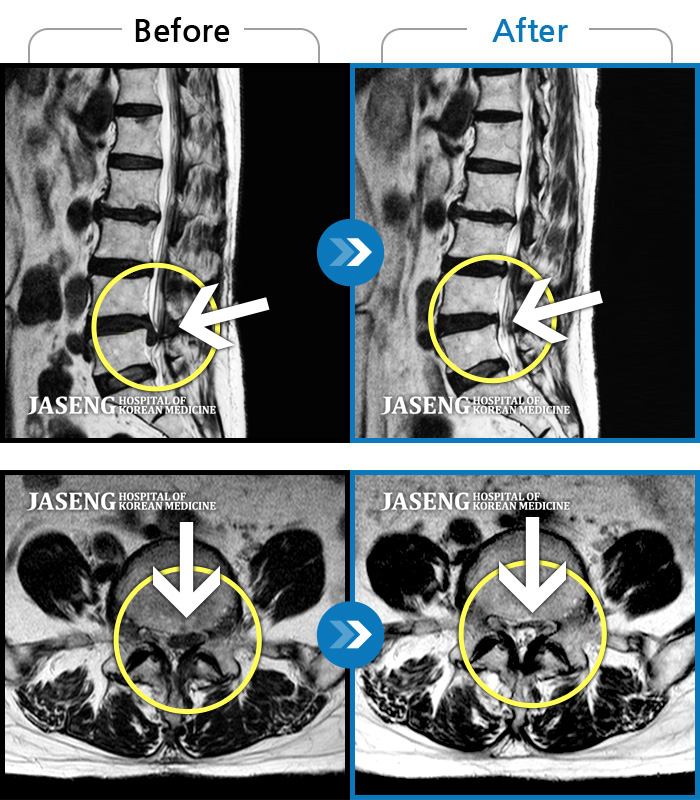

• 허리디스크

• 척추관협착증